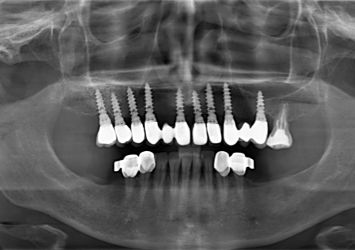

Rtg panoramiczne jest wykorzystywane na początku każdego leczenia stomatologicznego jako zdjęcie przeglądowe umożliwiające wstępną diagnostykę oraz ocenę stanu uzębienia , kości szczęki i stawów skroniowo-żuchwowych. W trudnych przypadkach leczenia na podstawie pantomografu pacjent jest kwalifikowany do dalszej diagnostyki tomograficznej. Możliwe jest również wykonanie rtg zatok przynosowych w różnych projekcjach oraz rtg warstwowe stawów skroniowo-żuchwowych.